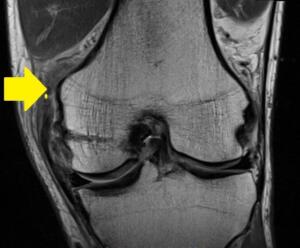

Per la diagnosi è importante ricostruire la dinamica dell’infortunio ed effettuare un’attenta visita clinica. Nella visita si valuta nello specifico dove è localizzato il dolore e mediante test clinici si saggia l’integrità dei legamenti riuscendo spesso ad avere un idea di quale legamento si è lesionato e della gravità della lesione stessa. A completamento diagnostico si possono utilizzare l’ecografia e/o la risonanza magnetica (alla quale è stato sottoposto Belotti) che permettono di definire con precisione maggiore il quadro dell’infortunio.

Quando si parla di distorsione del ginocchio si intende un evento che ha provocato uno stiramento oltre il limite fisiologico di almeno uno dei quattro legamenti del ginocchio (crociato anteriore e posteriore, collaterale mediale e laterale) portando un danno ad una parte o alla totalità delle fibre che li compongono. Le cause delle distorsioni sono: torsioni eccessive, traumi laterali o anteriori con piede puntato a terra, atterraggio errato da salti e altri movimenti che portano ad un eccessiva escursione dell’articolazione. La gravità della distorsione è classificata in 3 gradi, dal grado 1 in cui si ha una lesione parziale in meno del 10% delle fibre di un legamento fino al grado 3 quando tutte le fibre di un legamento sono danneggiate o interrotte.

La partita con il Verona è stata nefasta per i colori granata, il risultato maturato lascia più che un dubbio aperto e l’uscita in barella del gallo Belotti ha fatto temere il peggio per il proseguo del campionato. Successivamente agli esami clinici effettuati però l’infortunio del gallo è sembrato essere meno grave di quello che le immagini televisive avevano fatto temere. Il responso clinico è stato: lesione primo/secondo grado del legamento collaterale e capsulare mediale del ginocchio destro. Il ginocchio del calciatore è l’articolazione più soggetta a traumatismi ed in infortuni di variabile entità, dalle gravi rotture legamentose fino alle semplici contusioni. Questo avviene per diversi motivi: in primis la dinamica alla quale il calciatore sottopone le proprie articolazioni (acelerazioni, brusce decelerazioni, torsioni, salti etc.), in secondo luogo tutti gli impatti dell’arto con il terreno e per ultimo tutti i contatti ed i contrasti fisici. Bisogna ricordare che la stabilità del ginocchio è data dai legamenti crociati anteriore e posteriore, che formano una sorta di perno centrale, dai legamenti collaterali laterale e mediale, che impedisco le eccessive escursioni laterali dell’articolazione, e dai muscoli e tendini che permettono i movimenti.